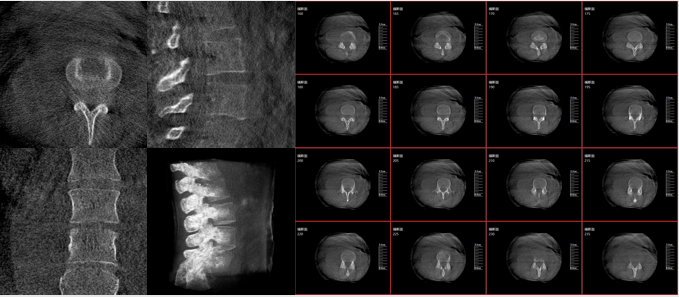

術(shù)中三維C臂通過不同方位的斷層圖像,能夠更清晰、完整地顯示椎體及其附件的解剖學(xué)結(jié)果,直觀地分析病變與周圍組織的立體空間關(guān)系,三維斷層成像能夠使手術(shù)模擬和手術(shù)方案的制定更加準(zhǔn)確。

而三維影像的MPR圖像組可以通過不同平面的切分,使成像區(qū)內(nèi)更豐富的信息得以呈現(xiàn)。尤其是二維影像無法涉及的橫斷面,提供了另一個空間維度的信息量。

術(shù)中三維C臂影像帶來的更加豐富的信息,可以作為醫(yī)生手術(shù)執(zhí)行的判斷基礎(chǔ),以及手術(shù)操作后實時的影像判斷依據(jù),從而保障手術(shù)效果。

在既往的手術(shù)中可能會出現(xiàn)這樣的情況:術(shù)后在影像科CT檢查中發(fā)現(xiàn)某個手術(shù)效果需要調(diào)整,這時往往需要返臺、翻修等才能解決。而術(shù)中三維C臂提供的術(shù)中三維影像功能可以將這一步驟合并至手術(shù)流程中,有效地降低醫(yī)患雙方的風(fēng)險,為手術(shù)保駕護(hù)航。